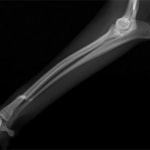

症例3:キルシュナーワイヤーのピンニングによる整復

ペルシャ猫 11ヶ月齢 雄

他院にて左大腿骨遠位の成長板骨折(salter-harrisⅠ型)が認められており、治療相談を目的として来院。当院にて、キルシュナーワイヤーを用いたピンニングにより骨折部位の整復を行いました。術後の経過は良好で、現在も経過観察中です。

術前レントゲン